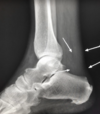

Método de imagen donde **no** se ve el ligamento pero sí los datos secundarios

Rx

Datos secundarios que se ven en la Rx | Esguince de tobillo

- Edema de tejidos blandos - Aumento del espacio entre peroné y astrágalo - Rx con estrés: “bostezo” - Descarta fracturas

¿Qué se ve en la Rx y TC de rotura del tendón de aquiles?

* Edema de tejido blando * Borramiento triangulo graso Kager * Descartar avulsión calcánea * Calcificación= crónico

¿Qué es esto?

Borramiento triángulo graso Kager = rotura del tendón de aquiles